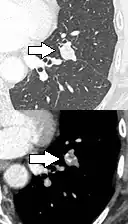

PET scan

If there is an intermediate risk of malignancy, further imaging with positron emission tomography (PET scan) is appropriate (if available). It can be done simultaneously as a CT scan in the form of PET-CT. Around 95% of patients with a malignant nodule will have an abnormal PET scan, while around 78% of patients with a benign nodule will look normal on PET (this is the test sensitivity and specificity).[15] Thus, an abnormal PET scan will reliably pick up cancer, but several other types of nodules (inflammatory or infectious, for example) will also show up on a PET scan. If the nodule has a diameter of less than one centimeter, PET scans are often avoided because of an increased risk of falsely normal results.[15][16][17] Cancerous lesions usually have a high metabolism on PET, as demonstrated by their high uptake of FDG (a radioactive sugar).

-

PET-CT of a tuberculoma.